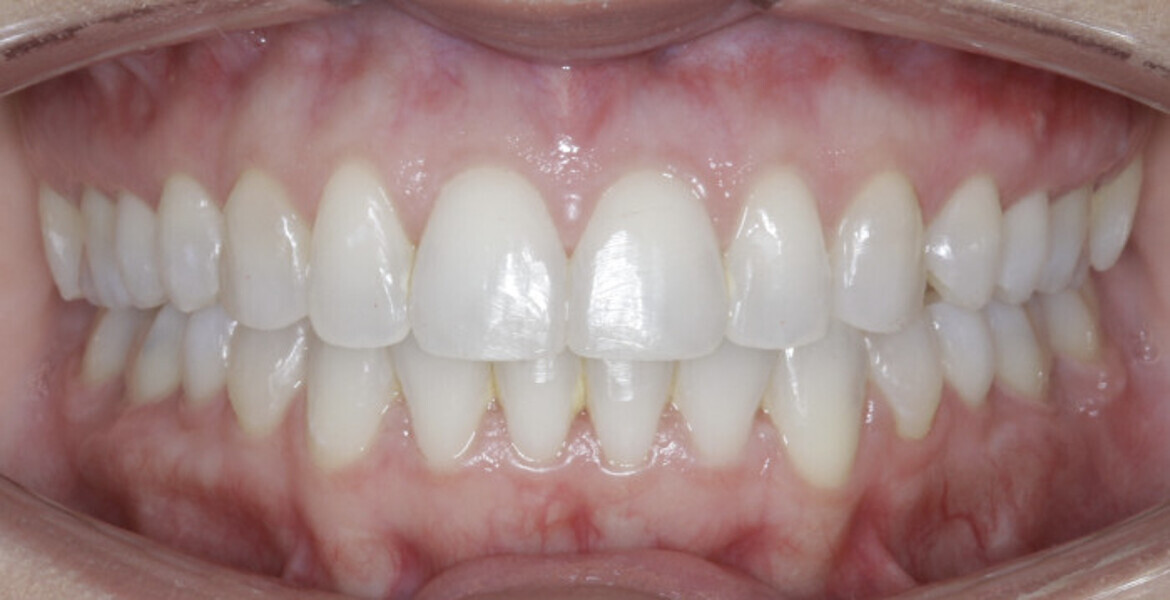

New Age orthodontics and orthopaedics with temporary anchorage devices